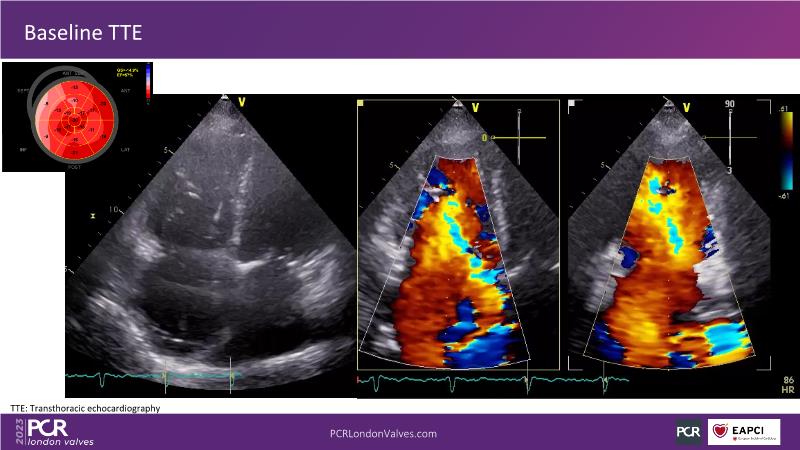

This session explores the features of the PASCAL Precision and the EVOQUE tricuspid replacement systems through simulators and case presentations, while a panel of experts discuss the technology, witnessing live demonstrations of treating mitral and tricuspid regurgitation patients.

- To learn about the differentiating features of the PASCAL Precision system showcased in a series of simulators alongside case presentations

- To interact with a panel of experts discussing the PASCAL Precision system technology and showcasing, live, its different key features in action and how they help treat mitral regurgitation and tricuspid regurgitation patients